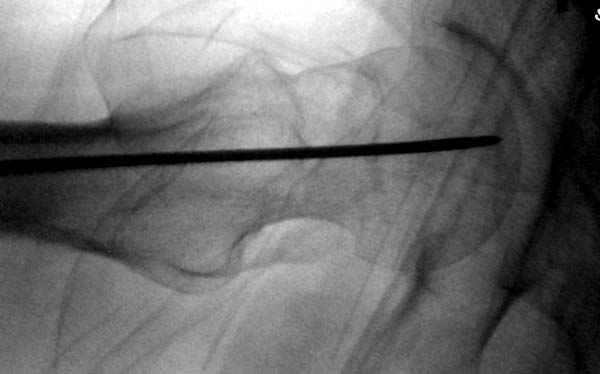

Профилактику дальнейшего раскола неполного перелома шейки провели тремя канюлированными шурупами.

На второй день после выписки упал дома. Снимки приложены. Коллеги рекомендуют удаление шурупа и вытяжение. Что делать?